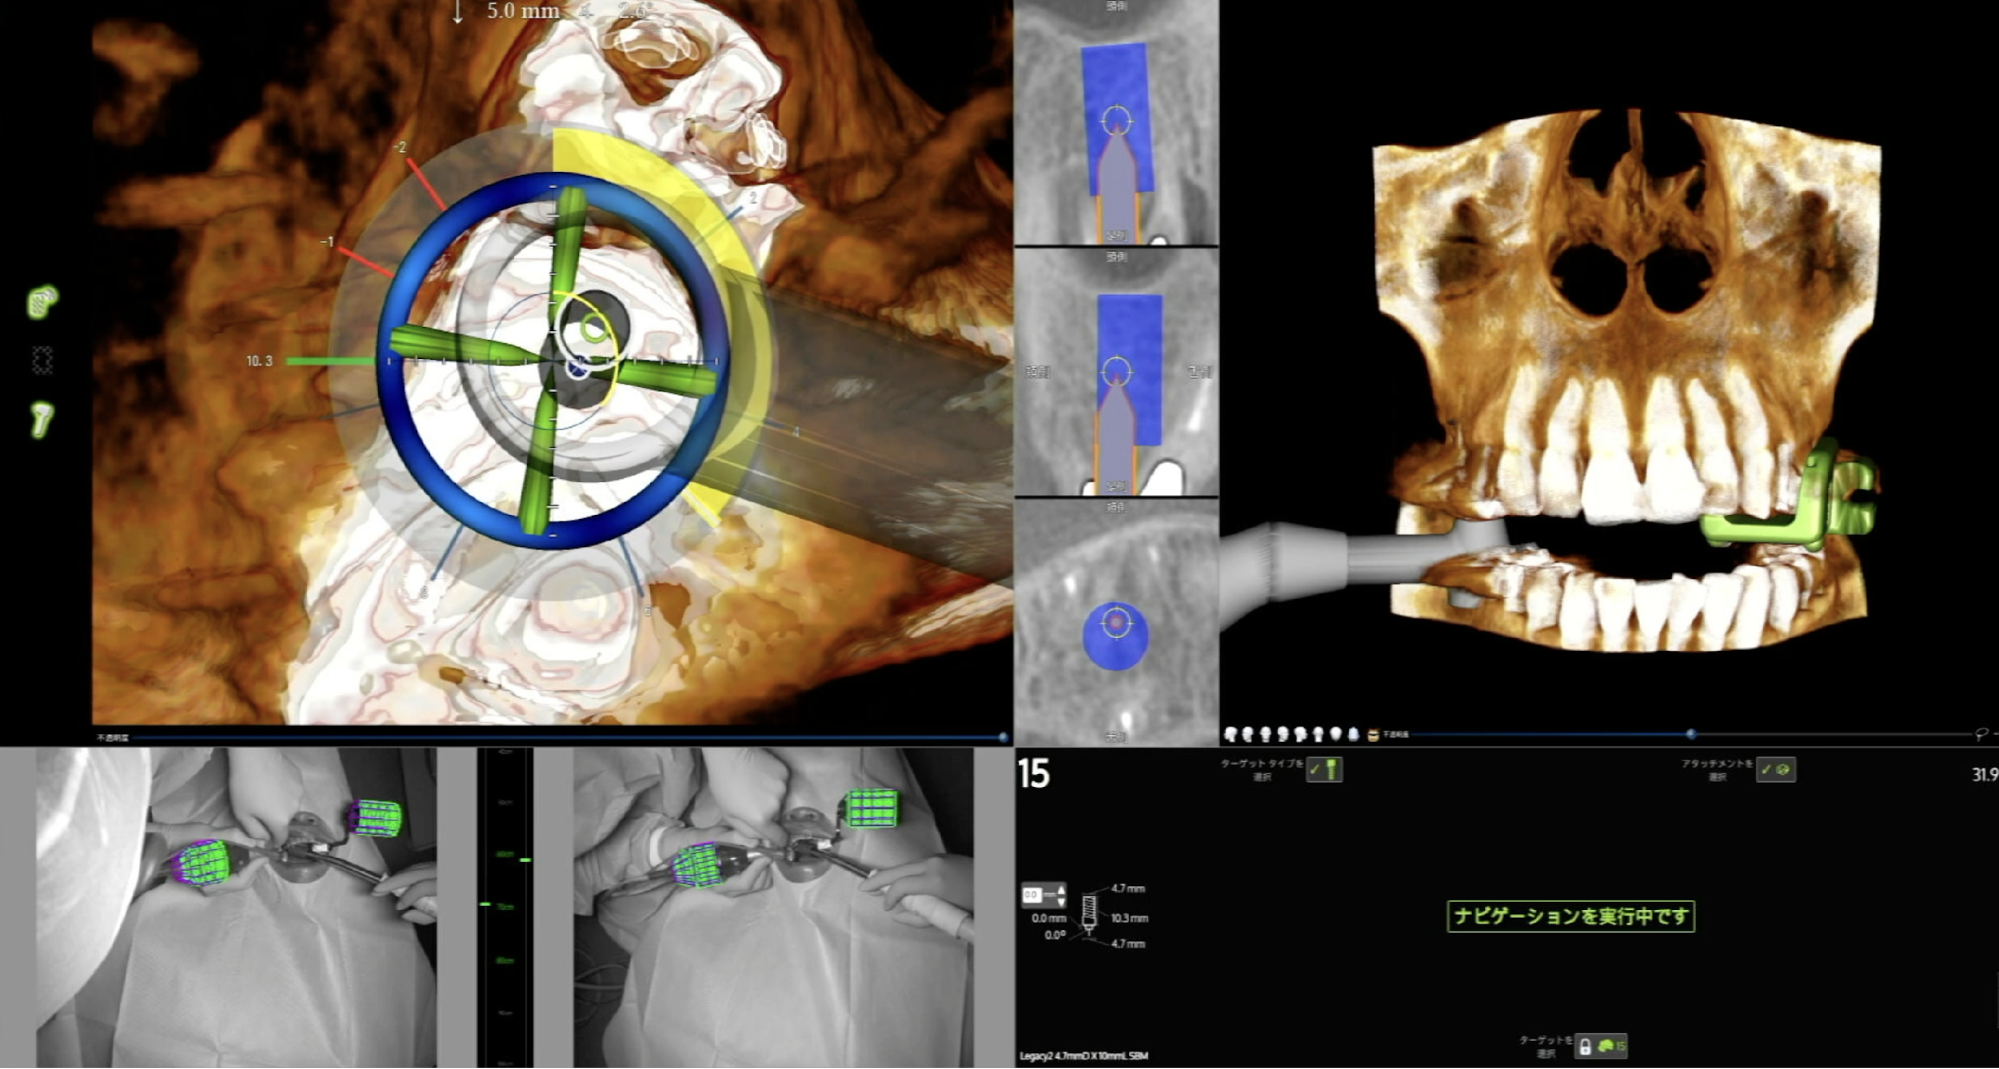

② Xガイドによるフラップレス埋入

ここからが当院のデジタル技術の真骨頂です。「Xガイド」を使用し、歯ぐきを切らずにインプラントを埋入していきます。

本来、歯ぐきを切らないフラップレス手術は、骨を直接見ることができないため、歯科医師の経験や勘に頼る部分があり、リスクも伴う高度な術式です。しかし、Xガイドを使うことで、そのリスクを軽減できます。

手術中、CT画像をもとに計画した「理想的なインプラントの位置・角度・深さ」と「現在のドリルの位置」が、リアルタイムでモニター上に表示されます。

これにより、歯ぐきを切開して骨を目視しなくても、画面上で骨の内部を透視するように確認しながら手術ができるため、安全確実なフラップレス手術が可能になります。

● ピンポイントの精度: 0.1ミリ単位の正確な位置に埋入できます。

● 低侵襲(傷口が小さい): フラップレス手術の安全性を担保する重要な機器です。

Xガイドの画面を確認しながら、計画通りの位置へピンポイントにインプラントを埋入しました。歯ぐきを切っていないため、出血はほとんどありませんでした。